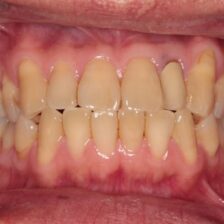

ダイレクトボンディングなどの

審美治療も高精度に対応